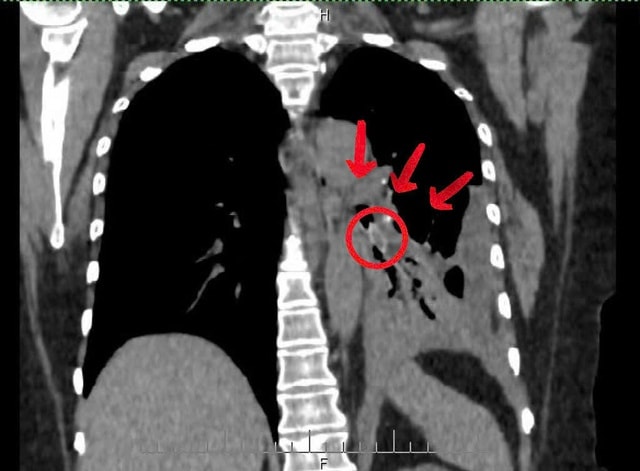

Ca thứ nhất là ông V.T.Đ. (65 tuổi, phường Quỳnh Mai, Nghệ An) nhập viện ngày 22/11 trong tình trạng khó thở, đau ngực trái. Kết quả chụp cắt lớp cho thấy có dị vật sâu trong đường thở. Ê - kíp cấp cứu phối hợp bác sĩ nội soi tiến hành can thiệp khẩn.

Qua nội soi phế quản, bác sĩ phát hiện một hạt hồng xiêm trơn bóng mắc tại phế quản phân thùy 4 - 5 trái, gây viêm mạnh và nhiều mủ trắng che kín lòng phế quản. Sau gần 30 phút thao tác tỉ mỉ, dị vật dài khoảng 2 cm đã được gắp ra an toàn.